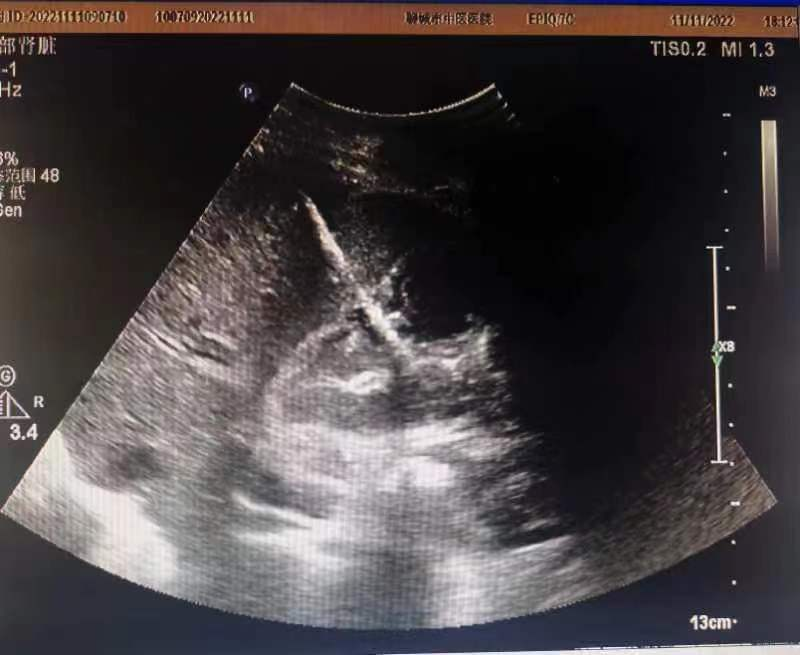

外二科李俊峰、赵洪浩、张潇医师团队联合超声科医师为患者实施了经皮肝脏穿刺胆囊置管引流术,皮切0.3cm小伤口,于超声引导下将穿刺针经皮肤切口、肝脏穿刺进入胆囊,穿刺过程顺利,患者无明显不适感,穿刺完毕引流出黄褐色脓液约300ml。术后第二天,患者进食较前有了明显改善,术后第3天便基本恢复到正常进食状态,各项指标趋于正常。

全程可见穿刺针,更精确,更安全